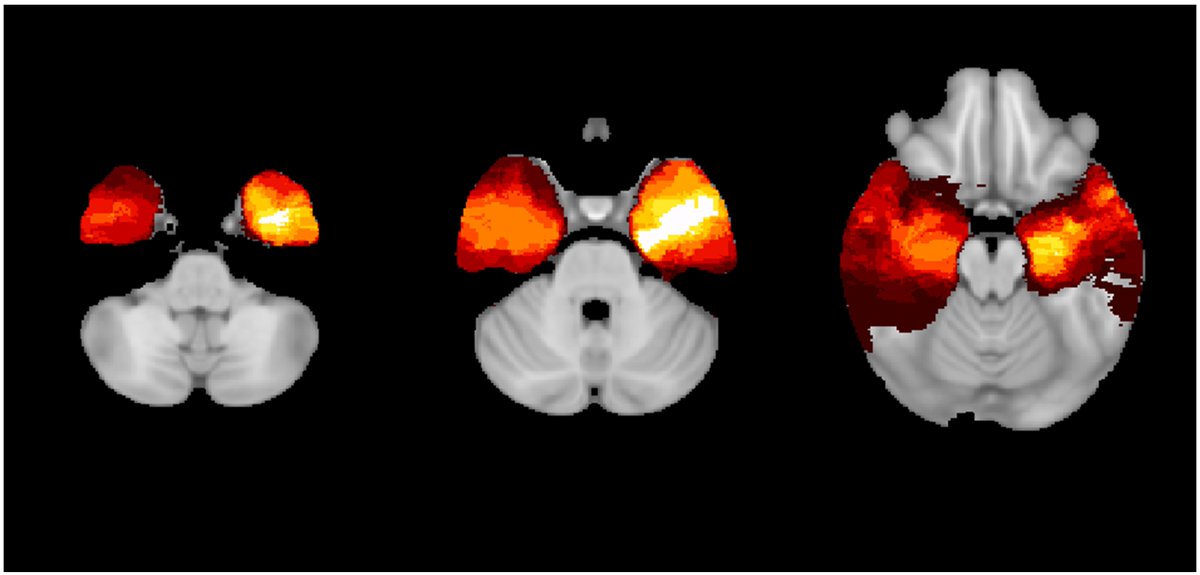

Lyndon proposes that functional neurological disorder reflects disordered precision control in predictive coding. Arousal can transiently over-amplify confidence in maladaptive predictions so that they override sensory feedback, giving rise to symptoms. shorturl.at/FYqYG